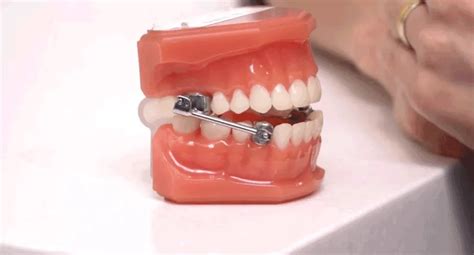

Jaw Wiring Procedure at Olivia Quinn blog